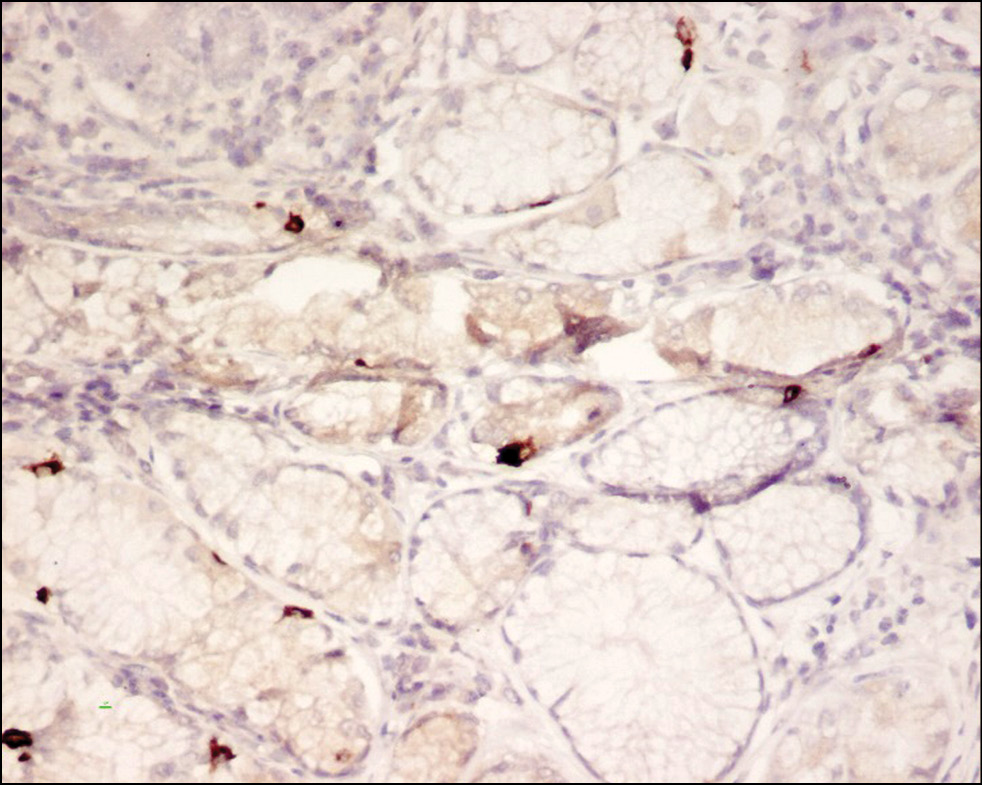

На основании иммуногистохимического анализа (рис. 1) было установлено, что иммуноморфологические данные пациентов с СРКд и СРКз статистически значимо отличались от группы контроля по плотности распределения ЭК в толстом кишечнике, продуцирующих мотилин, вазоактивный кишечный полипептид и соматостатин (p < 0,05). Так, среди пациентов первой группы с СРКд было зафиксировано статистически значимое увеличение числа ЭК, продуцирующих мотилин и вазоактивный кишечный полипептид, а также более низкие значения количества ЭК, секретирующих соматостатин, по сравнению с группой контроля (p < 0,05). В то же время в группе пациентов с СРКз было отмечено уменьшение плотности клеток, отвечающих за продукцию мотилина, вазоактивного кишечного полипептида, и увеличение количества клеточных элементов, секретирующих соматостатин (рис. 2–4), по сравнению с группой контроля (p < 0,05).

Рис. 2. Сигмовидная кишка больного с синдромом раздраженного кишечника с запором. Иммуногистохимический метод (× 200). Вазоактивный кишечный полипептид в клетках слизистой оболочки толстого кишечника

Рис. 3. Сигмовидная кишка больной с синдромом раздраженного кишечника с запором. Иммуногистохимический метод (× 200). Мотилин в клетках слизистой оболочки толстого кишечника

Рис. 4. Сигмовидная кишка больного с синдромом раздраженного кишечника с запором. Иммуногистохимический метод (× 200). Соматостатин в клетках слизистой оболочки толстого кишечника